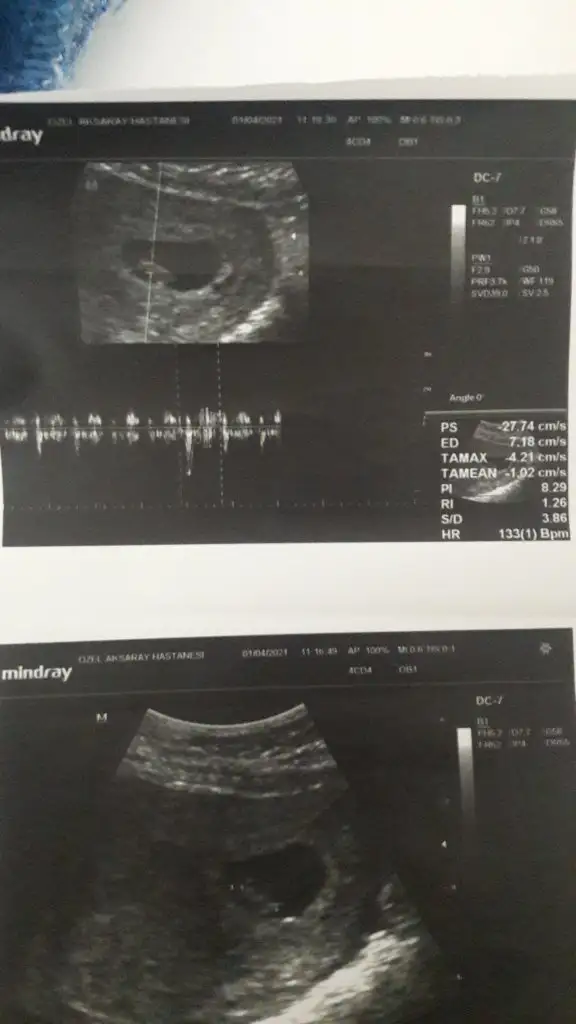

Banada bakarmisiniz

Eklentiler

• IMG-20210427-WA0184.webp

IMG-20210427-WA0184.webp

21,5 KB · Görüntüleme: 60

• IMG-20210427-WA0181.webp

IMG-20210427-WA0181.webp

23,4 KB · Görüntüleme: 56